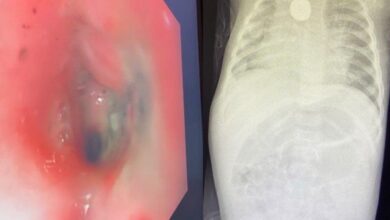

بطارية حارقة في مريء طفلة بمكة

أحوال – نوال مسلم : في سابقة علاجية نادرة دون تدخل جراحي، نجح فريق طبي بمستشفى الولادة والأطفال بالعاصمة المقدسة عضو تجمع مكة المكرمة الصحي في استخراج بطارية حارقة مختفية…